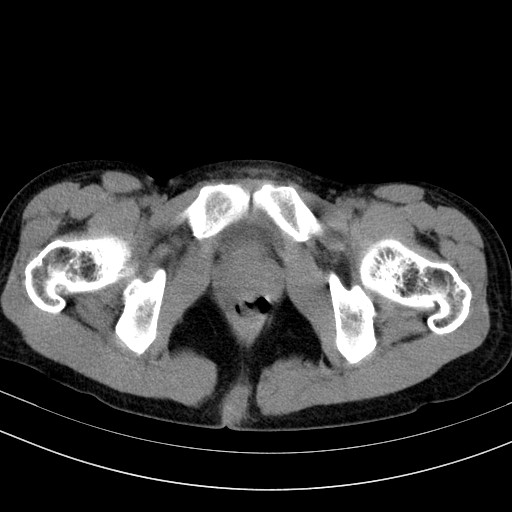

以下是引用随光逐影在2009-4-7 8:17:00的发言:[br]考虑宫颈占位性病变(宫颈癌?);建议行进一步检查。

以下是引用jiangjing在2009-4-7 16:46:00的发言:[br]宫颈增大,结构不清,右侧附件区可疑囊样占位,建议增强及mri 检查